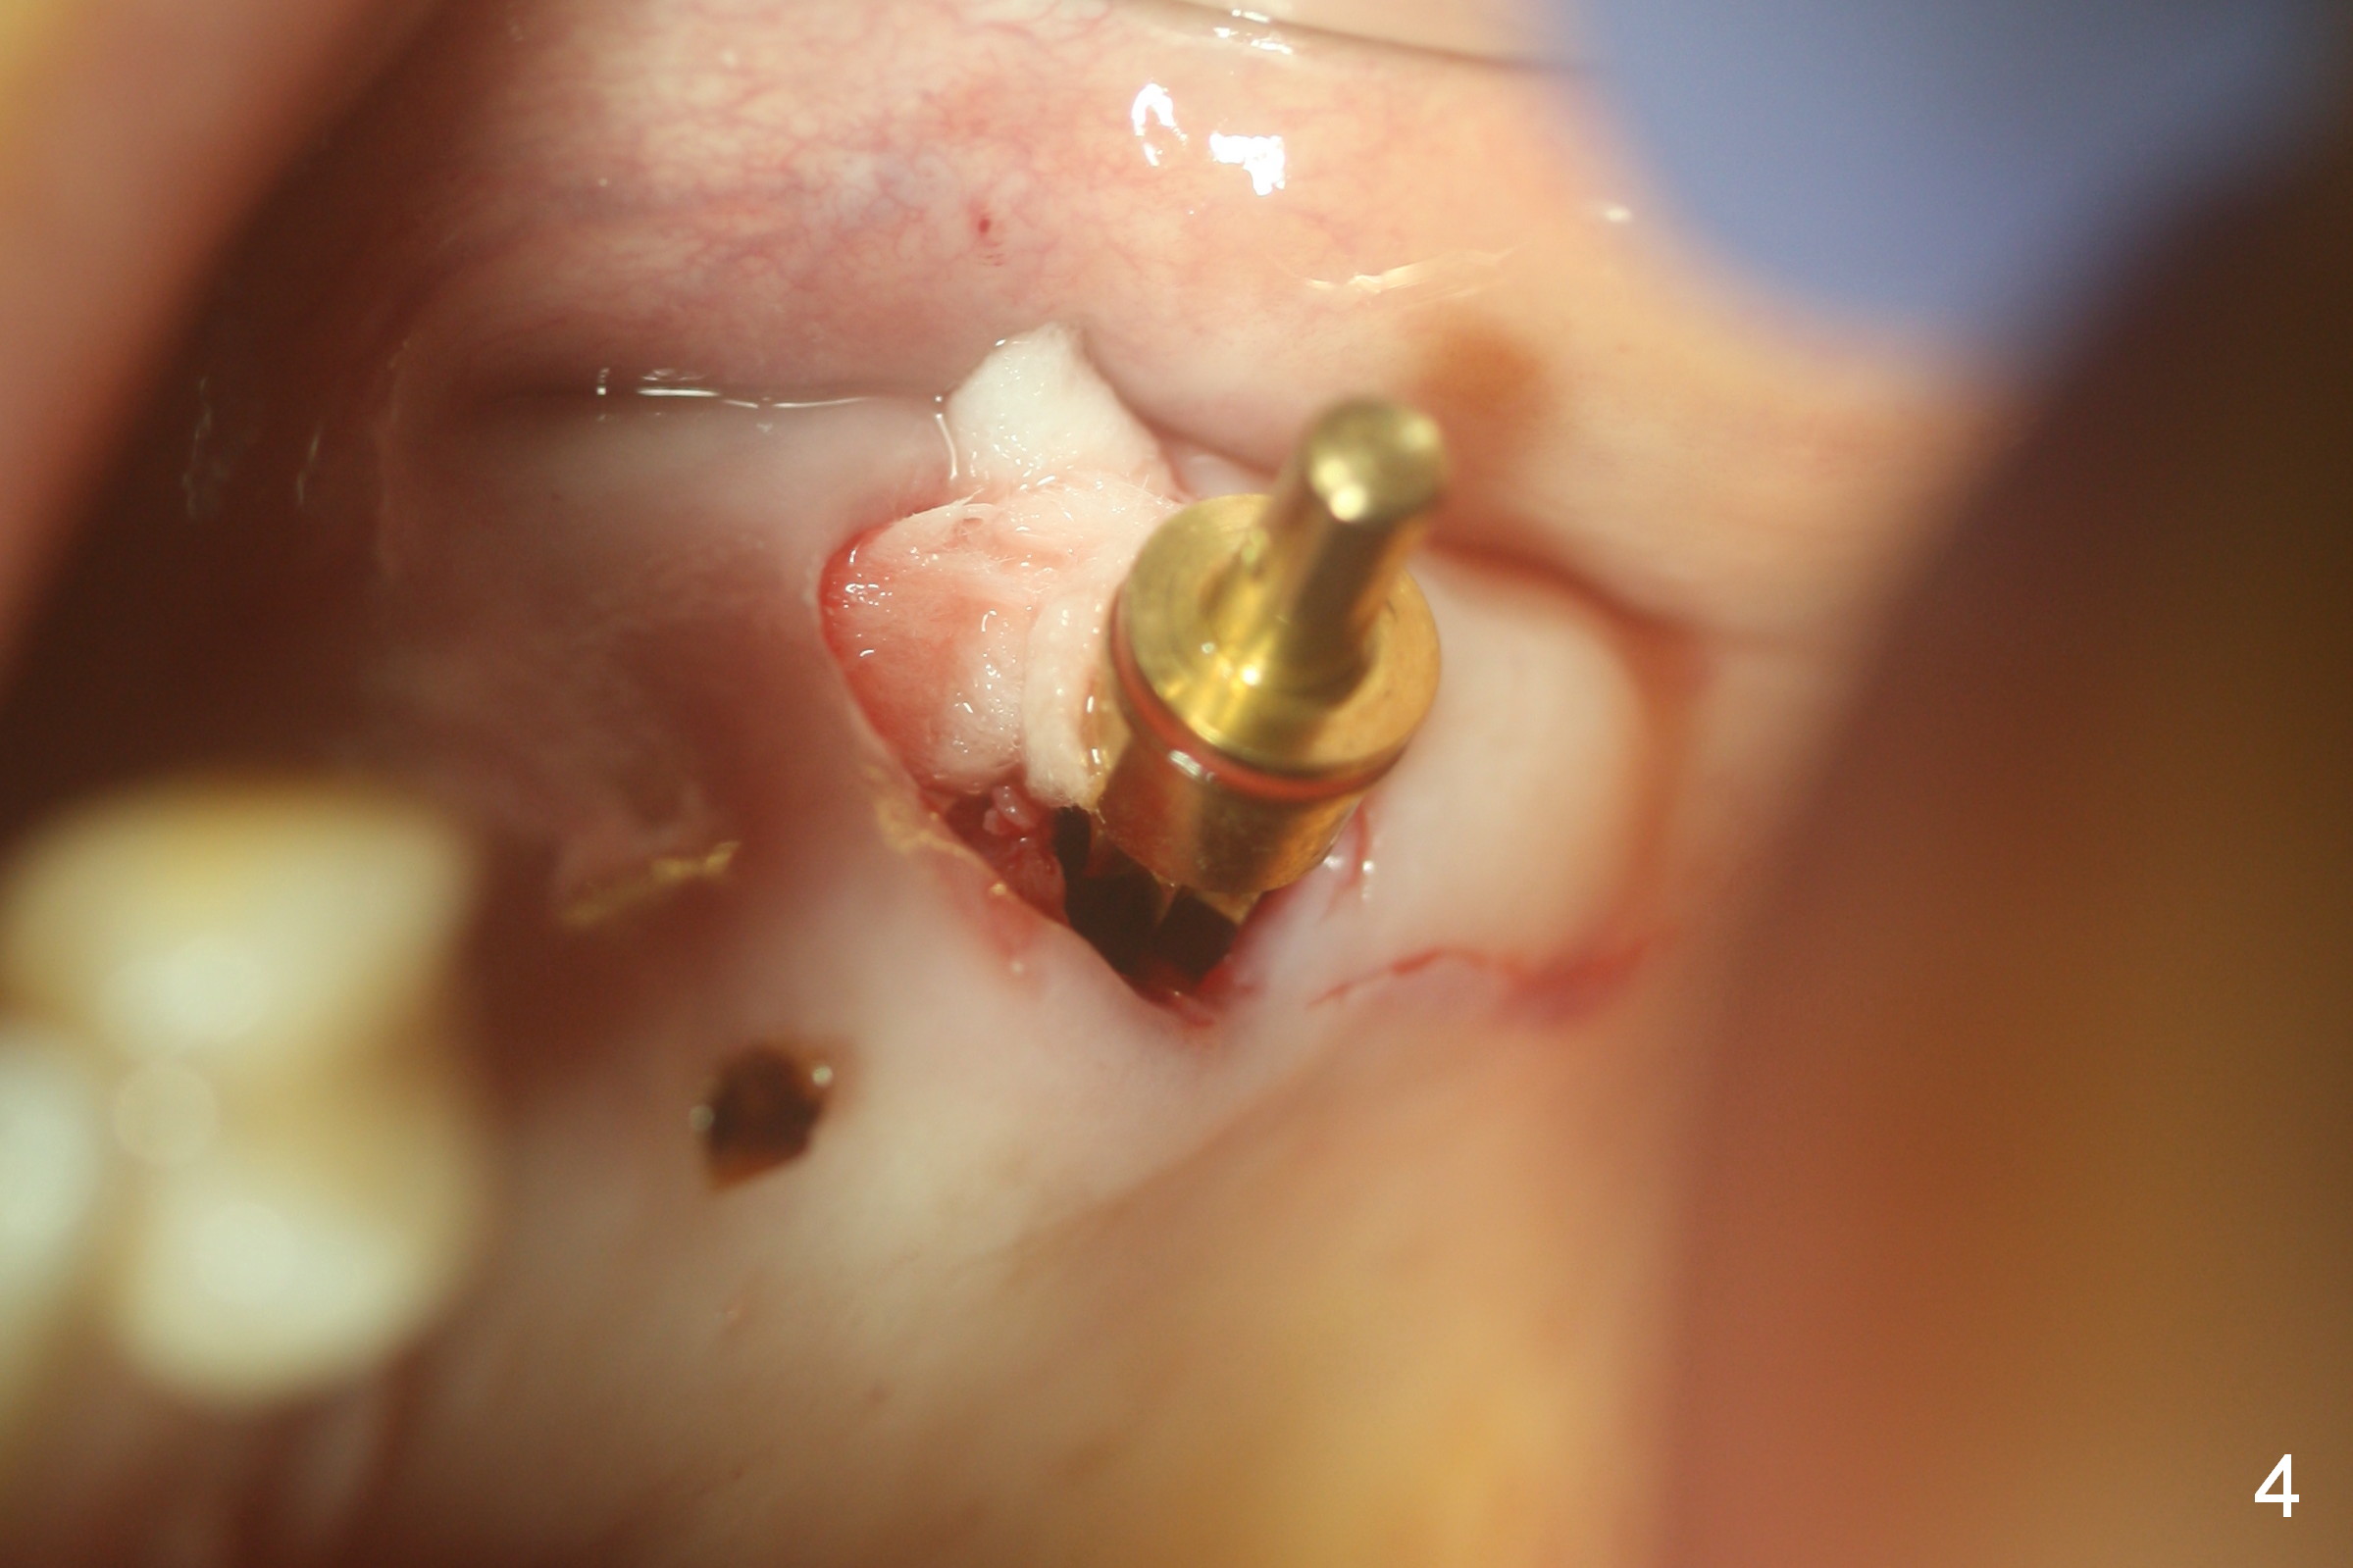

Fig.1,2 show the close relationship of the upper flipper and the residual roots at #15. Atraumatic extraction using periotomes and surgical sectioning still results in perforation of the mesiobuccal socket (Fig.3 >). The distobuccal one is shallow, while the septum is small. It appears that the palatal (Fig.3 P) socket is the most ideal recipient site for the immediate implant and is expanded with Magic Osteotomes until 4.3 mm (Fig.4,5) with the coronal end pushed as buccal as possible. After placing allograft for sinus lift (Fig.6 >), a 5x11 mm IBS implant is placed with insertion torque ~ 50 Ncm. A 6x4(3) mm pair abutment is placed, followed by bone graft in the remaining sockets (Fig.6 *) and by Osteogen plug (Fig.7 *). Finally the socket is sealed by applying acrylic over the abutment (Fig.8). While the acrylic is setting, the flipper is seated and excess acrylic is removed and pushed away from the flipper (Fig.9). Advise the patient not to wear the flipper. If it is being worn, there will be minimal contact between the flipper and the immediate provisional.